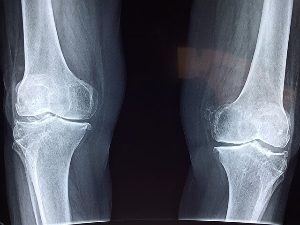

골다공증

뼈의 질량이 적어 뼈가 약해지고 골절되기 쉬운 특징의 질병입니다. 뼈 형성 과정과 뼈 흡수 과정의 불균형으로 인해 발생하며 이로 인해 뼈 덩어리가 손실되고 뼈 구조가 악화됩니다. 사람들은 나이가 들면서 자연스럽게 골밀도가 감소하고 30세 이후에는 뼈의 재흡수가 뼈의 형성을 앞지르기 시작하여 시간이 지남에 따라 골밀도의 감소로 이어집니다. 또는 폐경 후 여러 요인들로 인해 여성들이 남성들보다 골다공증에 걸릴 위험이 더 높으며 에스트로겐은 뼈 건강을 유지하는데 중요한 역할을 하는데 폐경 이후 에스트로겐 생산이 감소하면서 급격한 뼈 손실을 초래할 수 있습니다. 이 질병은 가족력이 있어 유전적인 영향을 미칠 수 있습니다. 또 갑상선 기능 항진증이나 내분비 질환, 류머티즘 관절염과 같은 염증성 질환, 위장질환등 특정 질환은 골다공증의 위험을 높일 수 있습니다. 건강한 몸에서 뼈는 끊임없이 분해되고 재건되는데 이 과정을 뼈 리모델링이라고 하고 리모델링이 차질을 빚거나 불균형이 생기면 재건보다 더 많은 뼈가 부서져 골밀도가 떨어지고 골절 위험이 높아집니다. 신체의 어떤 뼈에도 영향을 미칠 수 있지만 가장 흔한 골절은 엉덩이, 척추, 손목에 발생합니다. 골다공증으로 인한 골절은 만성 통증, 독립성 상실, 장애, 심지어 죽음을 포함한 심각한 결과를 가져올 수 있습니다. 이 질병의 위험 요인으로는 연령, 폐경, 가족력, 저체중, 골절력, 특정 진환, 특정 약물 그리고 앉아서 생활하는 생활 방식이 있습니다. 예방과 치료에는 칼슘과 비타민 D가 풍부한 식단, 운동이 좋으며 흡연과 과도한 알코올 섭취는 좋지 않습니다.